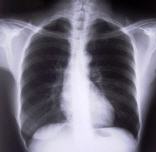

Lungen-Check

Woher kommt meine Kurzatmigkeit? Warum bin ich so schnell außer Atem?

In unserer Praxis bieten wir alle Möglichkeiten zur Lungenfunktionsdiagnostik an, einschließlich Sauerstoffsättigung. Damit können wir einen Großteil aller möglichen Lungenerkrankungen erkennen, ohne dass eine belastende Untersuchung mit Röntgenstrahlen durchgeführt werden muß.